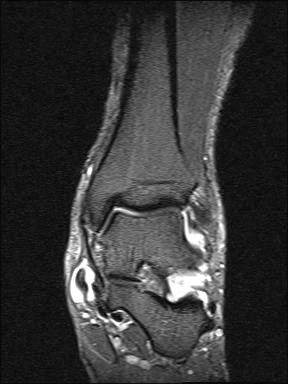

Aufgrund der geringen Zuverlässigkeit der klinischen Untersuchung und der konventionell radiologischen Bildgebung ist die Bildgebung der Wahl die Kernspintomographie (Szeimies 2014). Allerdings bestehen auch bei der Kernspintomographie klare Grenzen, vor allem hinsichtlich der Beurteilung der mechanischen Stabilität. Zuverlässige Aussagen sind möglich zum Ausmaß der Verletzung, insbesondere welche Bandanteile betroffen sind, sowie zu Begleitverletzungen. Chun et al. 11 berichteten über eine Sensitivität von 84% und eine Spezifität von 93,5% für Läsionen des Deltabandes im MRT. Befunde im MRT umfassen eine flächige Ödematisierung und Einblutung entlang des Deltabandes, meist unter Aussparung der kräftigen Pars tibiotalare posterior. Ein gewellter Verlauf, sowie eine Unterbrechung der Kontinuität der Faszikel sind Zeichen eines strukturellen Schadens. Teilweise finden sich Knochenkontussionsödeme, aber auch kortikale Absprengungen am lateralen Talusrand, der Talusschulter und am Außenknöchel. Fast immer findet sich ein Gelenkerguss (Abbildung 4).

Die zuverlässigste Beurteilung der mechanischen Stabilität des Deltabandes gelingt durch die diagnostische Arthroskopie (Abbildung 5)13.

Da bei der medialen Instabilität Befunde der MRT-Untersuchung entgehen können, wird bei Verdacht auf eine chronische Instabilität die ergänzende Arthroskopie empfohlen 13. Die dynamische Untersuchung des Sprunggelenks unter arthroskopischer Sicht ermöglicht die derzeit beste Beurteilung der Stabilität der medialen Bandstrukturen. Getestet wird die mediale und laterale vordere Schublade, die mediale und laterale Aufklappbarkeit, die Stabilität der Syndesmose und die generelle Laxizität des Gelenks durch axialen Zug. Neben der Stabilitätsbeurteilung ermöglicht die Arthroskopie eine Beurteilung der verletzten Strukturen, die Synovektomie mit Entfernung von freien Gelenkkörpern und die Abtragung von Osteophyten (Abbildung 7).